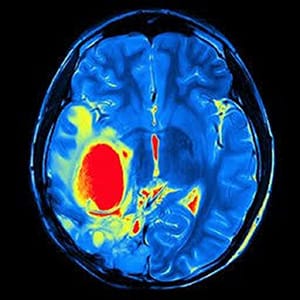

Hastamız kliniğimize başvurduğunda öncelikle detaylı bir nörolojik muayene yapıyoruz. Refleksleri, kas gücünü ve görme alanını inceliyoruz. Ardından kesin tanı koymak için İlaçlı Beyin MR (Manyetik Rezonans) veya BT (Bilgisayarlı Tomografi) tetkikleri istiyoruz. Bu görüntüler sayesinde tümörün yerini, boyutunu ve cinsini büyük oranda tespit ediyoruz.